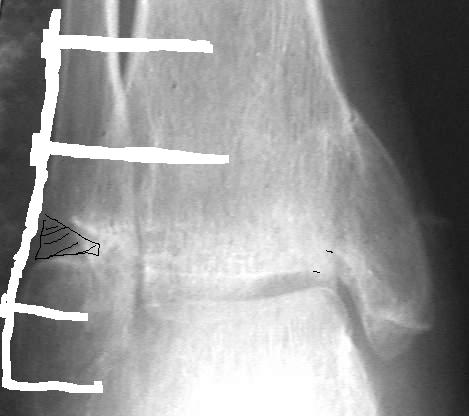

Провели костную аутопластику дефекта, металлоостеосинтез наружной лодыжки Г-образной пластиной и 4 винтами. Снимок 1, Снимок 2.

При проведении винтов выше перелома выявлен остеопороз. Есть опасность, что винты не удержат пластину при ранних нагрузках, поэтому провели винты через межберцовый синдесмоз.